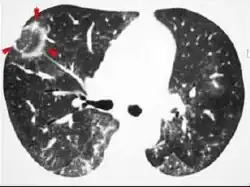

The chest x-ray is distinctive with features that appear similar to an extensive pneumonia, with both lungs showing widespread white patches. The white patches may seem to migrate from one area of the lung to another as the disease persists or progresses. Computed tomography (CT) may be used to confirm the diagnosis. Often the findings are typical enough to allow the doctor to make a diagnosis without ordering additional tests.[19] To confirm the diagnosis, a doctor may perform a lung biopsy using a bronchoscope. Many times, a larger specimen is needed and must be removed surgically.

Plain chest radiography shows normal lung volumes, with characteristic patchy unilateral or bilateral consolidation. Small nodular opacities occur in up to 50% of patients and large nodules in 15%. On high resolution computed tomography, airspace consolidation with air bronchograms is present in more than 90% of patients, often with a lower zone predominance. A subpleural or peribronchiolar distribution is noted in up to 50% of patients. Ground glass appearance or hazy opacities associated with the consolidation are detected in most patients.

Unusual presentations of organizing pneumonia

While patchy bilateral disease is typical, there are unusual variants of organizing pneumonia where it may appear as multiple nodules or masses. One rare presentation, focal organizing pneumonia, may be indistinguishable from lung cancer based on imaging alone, requiring biopsy or surgical resection to make the diagnosis.[20]